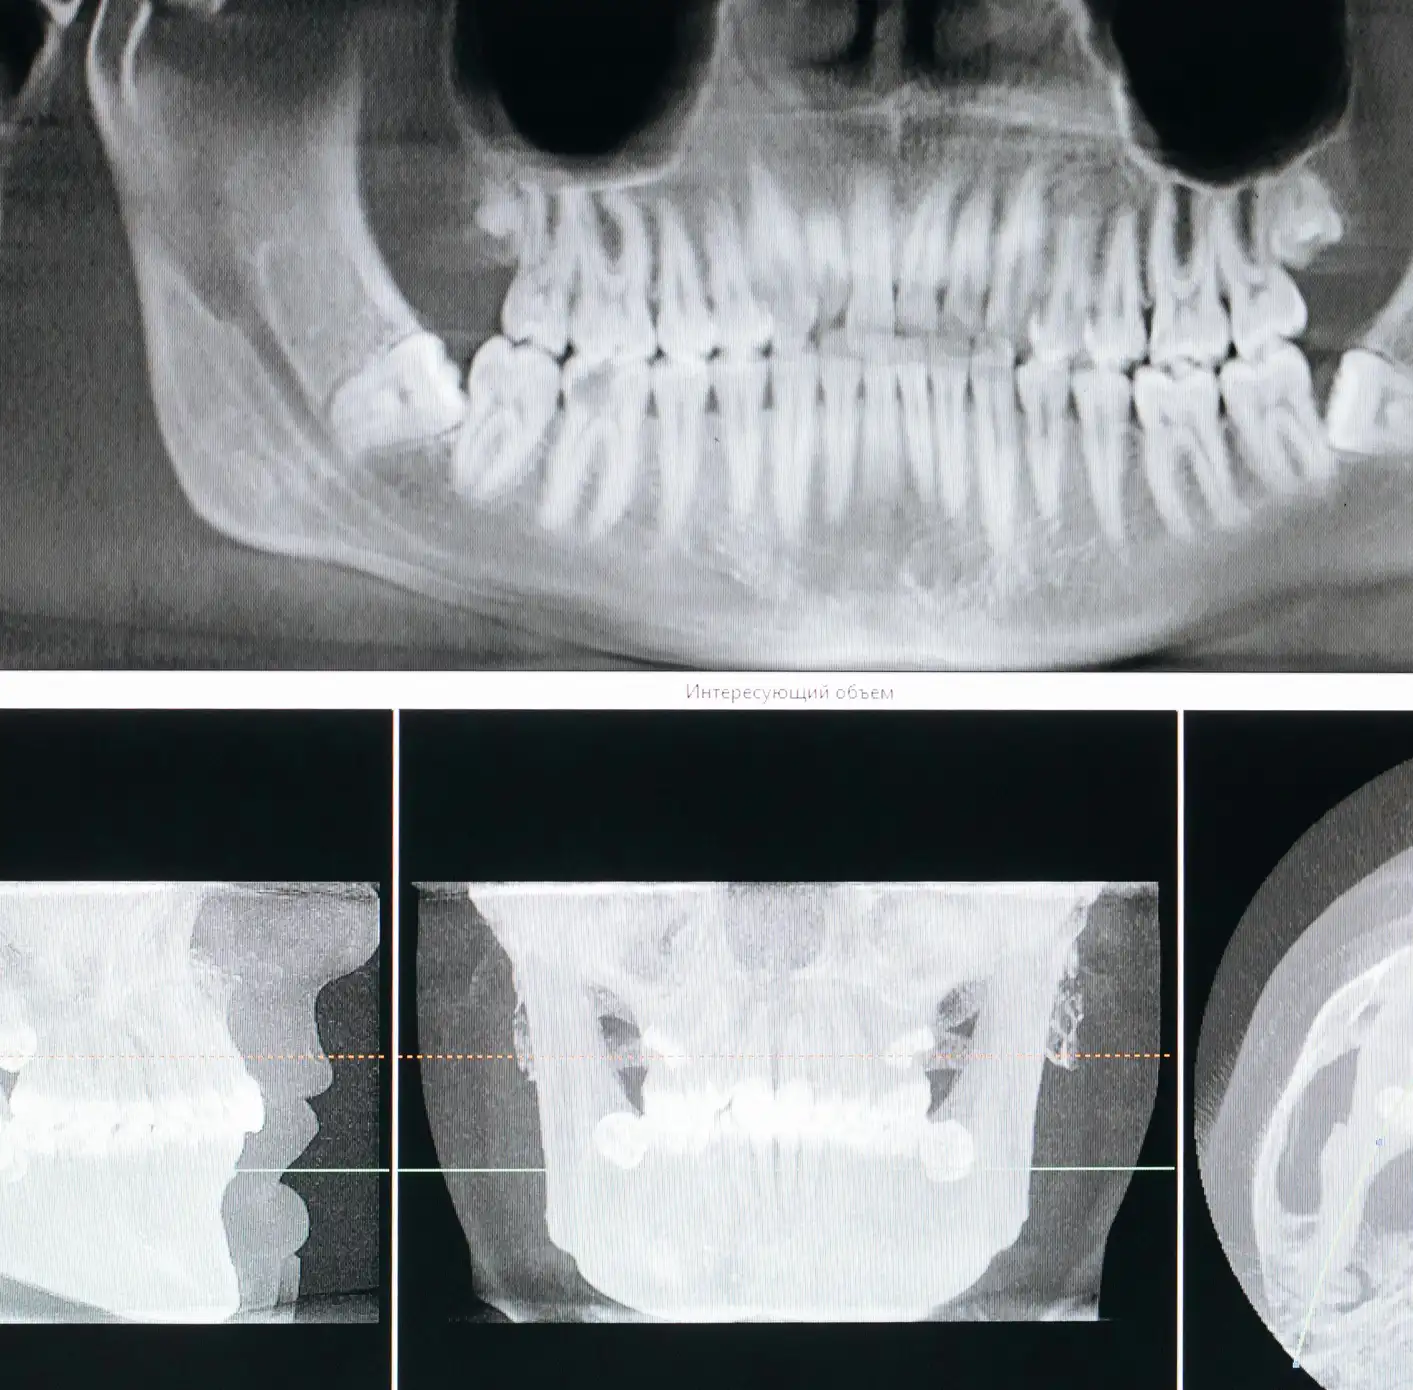

At Northwest Dental & Implant Centre, our dental implants offer a lasting solution for missing teeth. Whether you need a single tooth replacement or full permanent dentures, our expert team delivers natural-looking results that restore confidence, comfort, and function for life.